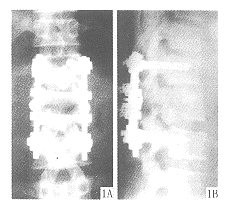

图1 L2爆裂骨折术后X线片

A.正位;B.侧位

1.3 手术方法 患者取俯卧位,垫高肩部和髂棘处,利用体位使骨折部分复位。在局部麻醉下手术,常规显露伤椎及相邻上下各一节段椎体棘突、椎板及横突根部。采用Weinstein法定位,定位点即椎体上关节突外侧缘纵轴线与同一椎体横突上下1/2水平线交点,定位器该点定位,椎弓根探子凭手感探入。根据不同节段,掌握不同的横切面角度,引道内置细克氏针。C形臂X线机透视,证实位置良好,置入角度椎弓根螺钉,置纵向连杆撑开、复位,恢复椎体轮廓,矫正后突畸形,锁定连杆。以临床症状较重及CT片所示椎管内骨块明显突出侧为减压侧。而脊髓受压最明显的部位多位于伤椎后上1/3~1/2,因此椎板减压范围上界至上位椎体下关节突的下半,下界至伤椎椎板中下1/3或椎板下缘,内侧至棘突根部,外侧至上关节突内侧半。咬除棘突根部前方及对侧椎板前方骨质,尽量扩大椎管矢状径,以利于硬膜牵拉向后移位,显露神经根,轻轻将硬膜向后、向对侧推移。暴露椎体后方骨块,用L形嵌压器将骨块嵌入椎体内。若嵌入困难,咬除骨块下方骨质后,再嵌入骨块。神经剥离子探查椎体对侧后缘情况,一般压迫均已解除。用细导尿管做减压区上下通畅试验。硬膜前方置明胶海绵,将咬除骨质或另取髂骨做伤椎及上下椎体横突间植骨,上R-F横向连杆(见图1)。伤口置负压引流管,术后卧床6~8周。

15例患者随访6~22个月,全部骨性融合(平均3~5个月),横突间骨桥连接,无感染、断钉、神经症状加重病例。测量脊柱术后侧位X线片,Cobbs角由术前平均25°矫正到术后平均6°。CT复查8例,显示椎管减压充分,脊髓受压解除完全。1例椎管容积减少仍>33%,但神经功能恢复良好,神经功能恢复见表1。